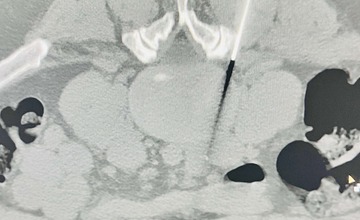

FOTO: V bánovskej nemocnici sa vďaka špičkovému CT prístroju začalo s poskytovaním ozónoterapie

Nemocnica AGEL Bánovce informuje, že v novovybudovanom CT pracovisku je od 13. júna v prevádzke špičkový a zároveň najpokrokovejší CT prístroj Incisive. Vďaka zriadeniu nového CT pracoviska sa tak v bánovskej nemocnici rozšírilo aj spektrum poskytovaných služieb.

Ozónoterapia je obľúbenou liečebnou metódou bolestivých stavov chrbtice a ide o miniinvazíny ambulantný zákrok, počas ktorého je ku koreňom miechy pod CT kontrolou aplikovaný medicínsky ozón.

„Zmes ozónu a kyslíka sa vyrobí v špeciálnom generátore ozónu, ktorý je súčasťou výbavy nášho CT pracoviska. Následne túto zmes podávame cez punkčnú ihlu injekčnou striekačkou do určeného miesta,“ vysvetľuje lekár CT pracoviska Abdolsalam Kazemi Jahromi.

Vysunutím medzistavcovej platničky v súčasnosti trpí čoraz viac pacientov. Z jadra platničky sa pri vysunutí uvoľňuje materiál, ktorý tlačí na miechové korene a spôsobuje bolesť. Ozón v mieste vpichu platničku vysuší, čím umožní jej vrátenie do pôvodnej polohy.

„Výhodou ozónoterapie je, že na rozdiel od medikamentóznej liečby bolestí chrbtice nemá prakticky žiadne vedľajšie účinky, ale úspešne pomáha s odbúraním bolesti,“ dopĺňa doktor A. Kazemi.

Podľa skúseného odborníka tento zákrok nie je veľmi príjemný, niektorým pacientom môže prísť nevoľno, cítia počas vpichovania miernu bolesť alebo tlak, no ozónoterapia je bezpečnejšia, menej invazívna a ľahšie zvládnuteľná ako neurochirurgická operácia.

Pacienta na ozónoterapiu štandardne posiela neurológ, prípadne ortopéd. Ako všetky druhy liečby, ani táto terapia nie je vhodná pre každého. Zákrok sa neodporúča pacientom v seniorskom veku, tehotným ženám, ľuďom s akútnou infekciou či hypertenziou.

Ozónovú terapiu v bánovskej nemocnici realizujú každý utorok, pacienti sa môžu vopred objednať na telefónnom čísle 038/76 24 313. V prípade potreby je možné po predošlej konzultácii ozón aplikovať aj pacientom s akútnymi ťažkosťami.